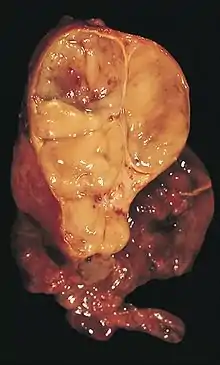

An encapsulated thymoma (mixed lymphocytic and epithelial type)

A thymoma is a tumor originating from the epithelial cells of the thymus that is considered a rare malignancy. Thymomas are frequently associated with neuromuscular disorders such as myasthenia gravis;[1] thymoma is found in 20% of patients with myasthenia gravis.[2] Once diagnosed, thymomas may be removed surgically. In the rare case of a malignant tumor, chemotherapy may be used.